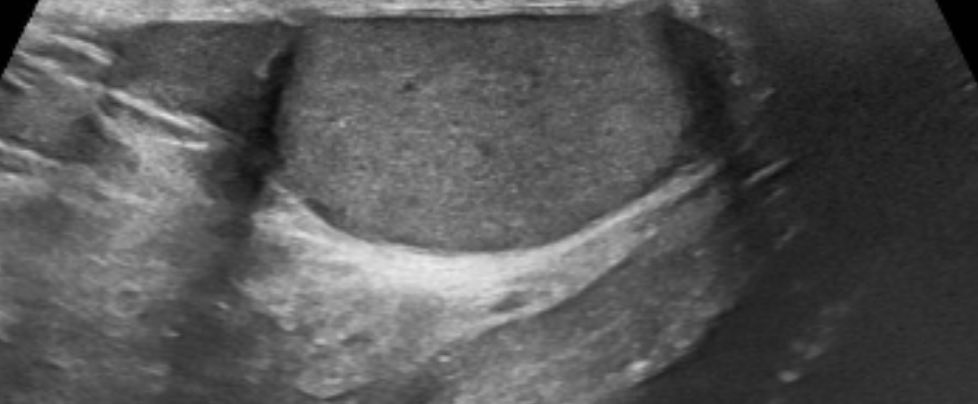

في رحاب منى، جمعتني هذه الصورة بأخي الذي ولدته لي الأيام HaniBadahdah, MD تعاهدنا أن نكون صوتاً و احداً في التوعية، وعملاً مستمراً لمحاربة #البتر رسالتنا الوقاية أولاً، والعلاج مبكراً ، والبتر ليس حتمياً #القدم_السكرية #وعي_وحياة #حج_1446 #حج_بصحة